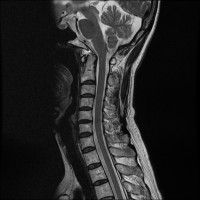

경추 요추 디스크 둘다 있는 상태고 경추몇번에서 몇번사이 요추몇번에서 몇번사이인지 알려주세요

목

• 1번 째 사진